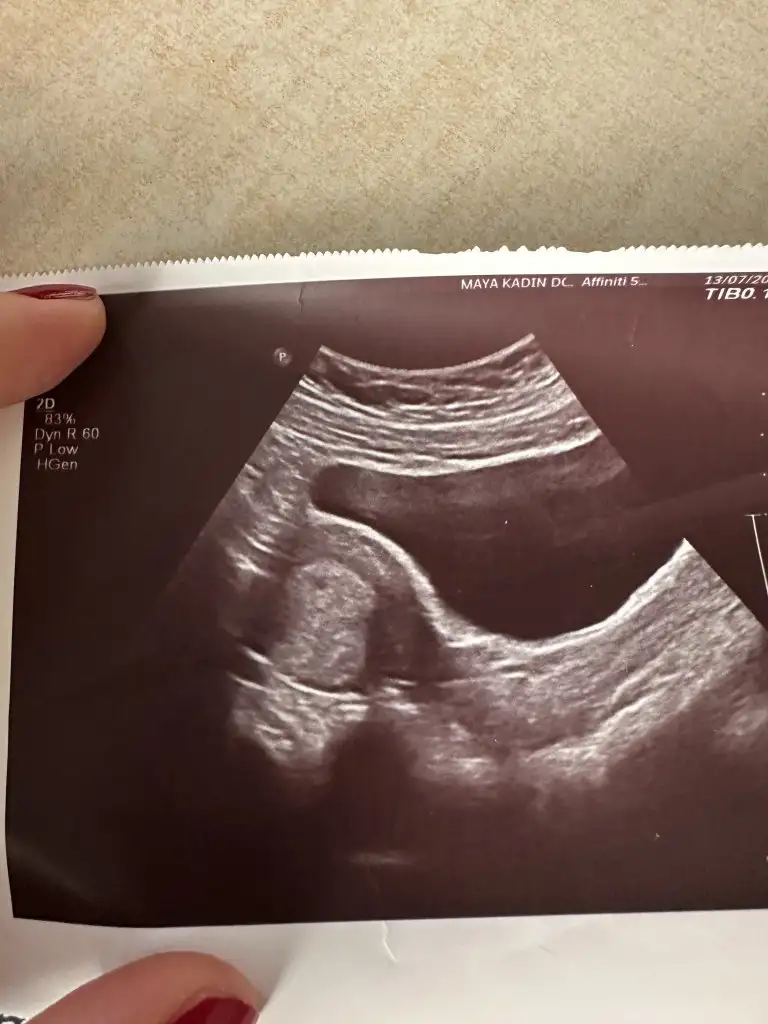

Kızlar ben geldım🥹 4+6 uyumlu cıktı bıde fotograf verdı heyecandan baska hıcbısey sormayı unuttum🥹😁 fnd_50 fnd_50 melegim can melegim can ,annem kızdı ıkıde bı karından ultrason olunmaz zararlı olabılır dedı😁😁

Ya yerim senin o minnoşun kesesini severim 🥹 annen haklı akıllı dur doktor ne zaman derse o zaman git🤭🤭🤭